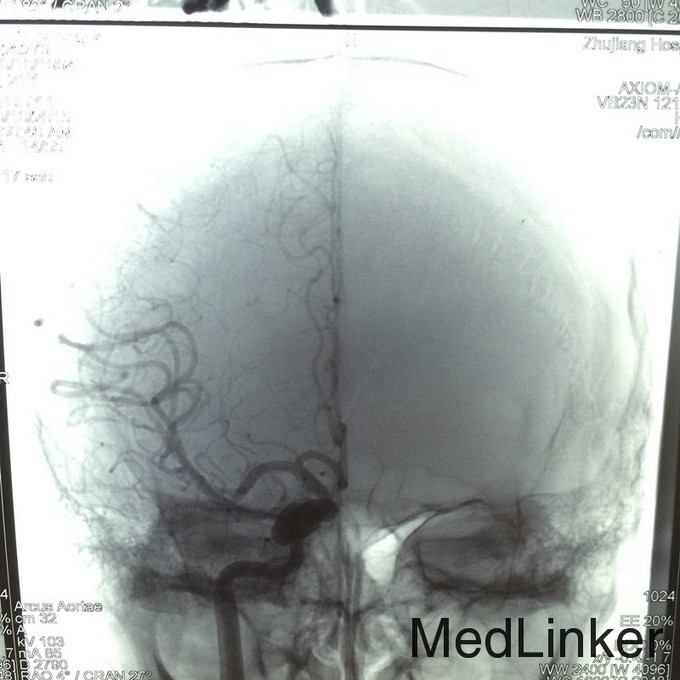

查体:右侧眼球突出,伴外展活动受限 辅助检查:头颅DSA提示右侧CCF

诊断:右侧自发性颈动脉海绵窦瘘 治疗:行头颅DSA检查,并用可脱性球囊将瘘口栓塞治疗

随访:患者症状消失出院 讨论:该患者无明显外伤史,头颅DSA证实为CCF,考虑为自发性引起。颈动脉海绵窦瘘是指海绵窦段的颈内动脉本身或其在海绵窦内的分支破裂,与海绵窦之间形成异常的动静脉沟通,少数颈动脉海绵窦瘘由颈外动脉供血,特称颈外动脉海绵窦瘘。75%以上的为外伤引起,称为外伤性CCF,其余无外伤史者,称为自发性海绵窦瘘。最常见的症状是搏动性突眼和球结膜充血、水肿。首选介入神经放射治疗,经导管将气囊或弹簧圈等栓塞材料放置在痿口处,封闭瘘口,可消除头颅杂音,使眼球回纳,恢复眼球运动。对复发者可再次治疗。